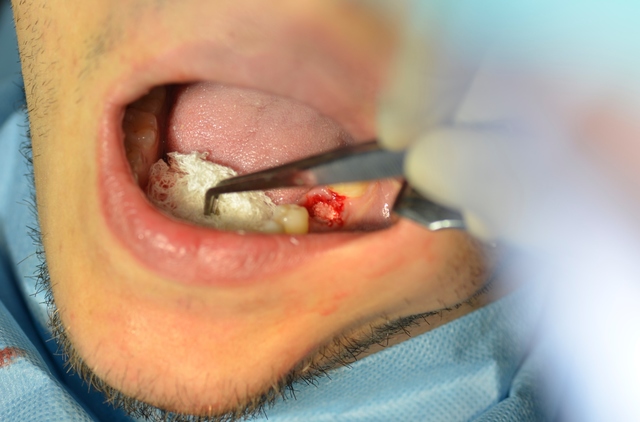

W znieczuleniu miejscowym przeprowadzono minimalnie inwazyjny zabieg usunięcia zęba metodą separacji korzeniowej. Następnie założono szablon implantologiczny i używając systemowej sekwencji wierteł, wypreparowano łoże pod wszczep, który następnie wprowadzono, uzyskując stabilizację pierwotną; zabezpieczono go śrubą zamykającą (Implant Seven, MIS). Wolne przestrzenie zębodołu poekstrakcyjnego wypełniono materiałem kościozastępczym (Bio-Oss, 0,25-1 mm, Geistlich Biomaterials, Szwajcaria), a całość pokryto błoną z osocza bogatopłytkowego oraz lateksowym koferdamem, utrzymywanymi szwami, które pozostawiono na 7 dni (ryc. 7-13).

Ryc. 10. Uszczelnienie zębodołu materiałem kościozastępczym.

Ryc. 11. Zaopatrzenie zębodołu błoną z PRF.

Ryc. 12. Rana zaopatrzona szwami i koferdamem lateksowym.